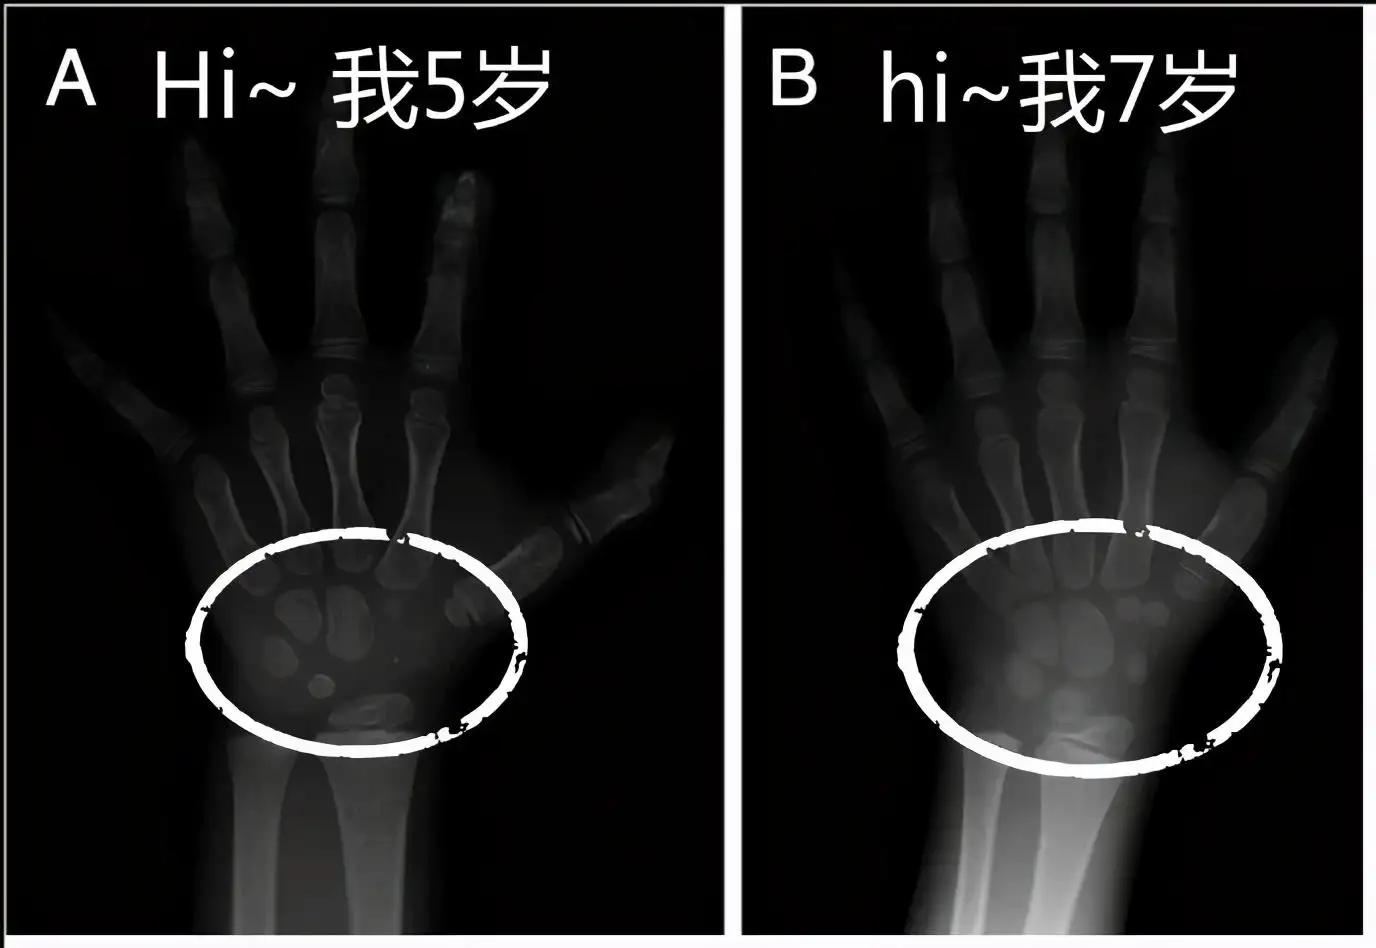

一、什么是骨龄?

以小儿骨骼实际发育程度同标准发育程度进行比较,所求得的一个发育年龄。骨龄在很大程度上代表了孩子真正的发育水平,因此用骨龄来判定孩子的发育情况比实际年龄更为确切。